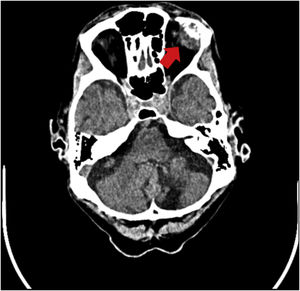

Paciente varón de 83 años sin antecedentes de interés que consulta por proptosis y diplopía en el ojo izquierdo de reciente comienzo. Se realiza tomografía craneal (fig. 1) y resonancia magnética (fig. 2) donde se objetiva masa heterogénea en la glándula lacrimal izquierda con invasión ósea del reborde orbitario supero-lateral. Se biopsia la lesión lacrimal descrita, evidenciándose datos compatibles con lesión metastásica de origen intestinal. Dados los hallazgos se realiza estudio de extensión, evidenciándose adenocarcinoma de recto superior avanzado (T3N2bM1c), asociado a metástasis hepáticas y óseas. Debido a lo avanzado de la enfermedad fue tratado con radioterapia paliativa orbitaria y quimioterapia paliativa.